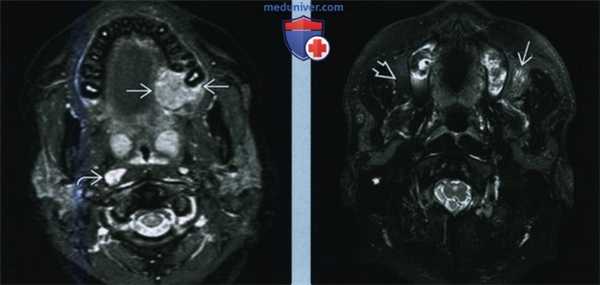

(Слева) При КТ с КУ в области правой небной миндалины определяется крупное новообразование пониженной плотности. Наличие четкой границы с окологлоточной клетчаткой позволяет думать, что опухоль не прорастает латеральную капсулу. Однако отмечается утолщение в области предпозвоночных мышц справа - свидетельство инвазии задней капсулы небной миндалины.

(Справа) Крупная экзофитная неходжкинская лимфома, минимально накапливающая контраст. Опухоль развивается из лимфоидной ткани левой половины язычной миндалины и практически полностью закрывает просвет дыхательных путей. Обратите внимание на лимфоузел IIA уровня без участка центрального некроза; это достаточно распространенная находка при лимфоме лимфоузлов. (Слева) При МРТ Т1ВИ в сагиттальной проекции определяется обширное образование носоглотки, которое опускается до уровня ротоглотки. Аномальная интенсивность сигнала в области ската говорит о поражении центральных отделов основания черепа.

(Справа) MPT Т2ВИ FS в аксиальной проекции, этот же пациент. Интенсивность сигнала достаточно низкая, опухоль распространяется в предпозвоночные мышцы и окологлоточное пространство. Обратите внимание на затемнение клеток сосцевидного отростка, которое возникло из-за прорастания опухоли в область устья слуховой трубы. Рак носоглотки может выглядеть абсолютно идентично.